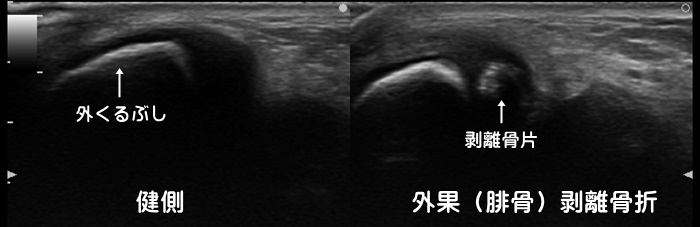

脛骨・腓骨剥離骨折

足首を捻挫した際に、靭帯に牽引されて内くるぶしや外くるぶしの先端が剥離骨折する事があります。ある統計では10歳以下:77% 11~14歳:19% 15~18歳:13%で剥離骨折が発症すると言われています。一般に子供の場合、靭帯よりも骨の方が弱い為、捻挫をすると靭帯断裂よりも剥離骨折が多く発症します。炎症反応の動画はこちらで確認できます。